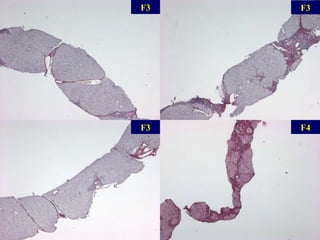

F3 F3 F3 F4

Scores de fibrose cirrhose Nbx ponts fibreux qq ponts fibreux Fibrose portale sans septa Pas de fibrose METAVIR 1994 cirrhose, probable or certaine 6 Nbx ponts fibreux, qq nodules (cirrhose incomplète) 5 Nbx ponts fibreux,  (EP-EP ou EP-CL) cirrhose 4 qq ponts fibreux Ponts fibreux (EP-EP ou  EP-CL) 3 Expansion fibreuse de la plupart des EP 2 Expansion fibreuse de qq EP Fibrose portale sans septa 1 Pas de fibrose Pas de fibrose 0 Ishak 1995 Knodell 1981   Score